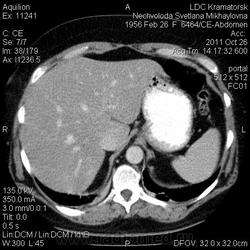

Здравствуйте! Вот уже месяц не могут поставить диагноз. Первичный очаг найти не удалось. Множественная миелома (несекретирующая?, т.к. по крови стерн. пункция не дает результата)?

Была взята биопсия с пораженного позвонка, но в материале оказалось мало клеток кости, наличие фиброзных клеток. Материал трепанбиопсии правой подвздошной так же содержал мало клеток, т.к. удалось углубиться всего лишь на 7мм (дальше сломалась игла, по словам врача скорее всего об фиброзное образ.). Можно ли по результатам КТ предложить повторный, более прицельный поиск? Что еще говорит КТ?

По имеющимся файлам-дайком я не нашла признаков опухоли. Имеется множественное остеолитическое поражение позвоночника, ребер, грудины, частично - таза. Лимфоузлы не увеличены. Тоже поставила бы на первое место миеломную болезнь. Диагностирование её не всегда простое дело. Поражена грудина и, наверное, нужно посоветоваться с онкологом (гематологом) стоит ли сделать стернальную пункцию.Советую написать в личку tatyana.

Думаю тоже в первую очередь здесь миеломная болезнь, процентов на 80%. Но результаты лабораторных анализов действительно неоднозначные.

Повторюсь: по имеющимся данным наиболее вероятной считаю миеломную болезнь